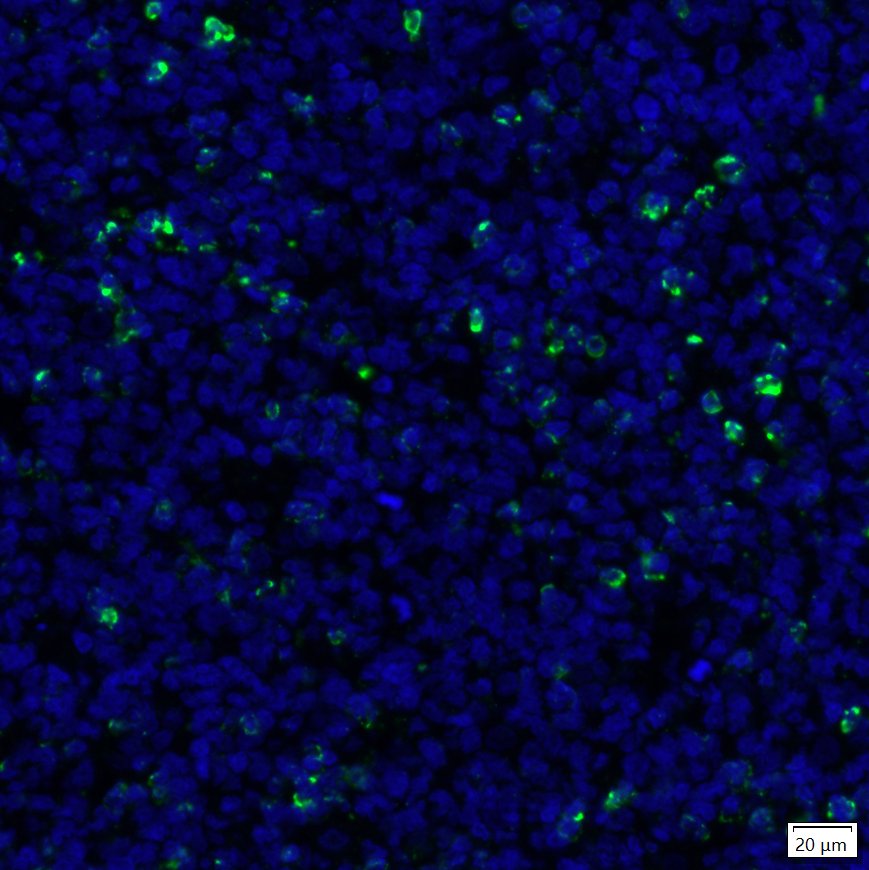

Immunocytochemistry analysis of NIH/3T3 cells transfected with or without LAG-3 labeling LAG-3 with Rabbit anti-LAG-3 antibody (HA721358) at 1/100 dilution.

Cells were fixed in 4% paraformaldehyde for 10 minutes at 37 ℃, permeabilized with 0.1% Triton X-100 in PBS for 15 minutes, and then blocked with 1% BSA for 30 minutes at room temperature. Cells were then incubated with Rabbit anti-LAG-3 antibody (HA721358) at 1/100 dilution in 2% negative goat serum overnight at 4 ℃. Goat Anti-Rabbit IgG H&L (iFluor™ 488, HA1121) was used as the secondary antibody at 1/1,000 dilution. Nuclear DNA was labelled in blue with DAPI.

Beta tubulin (M1305-2, red) was stained at 1/100 dilution overnight at +4℃. Goat Anti-Mouse IgG H&L (iFluor™ 594, HA1126) was used as the secondary antibody at 1/1,000 dilution. -